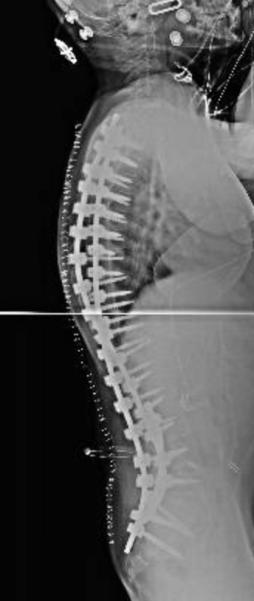

Qui di seguito, un esempio di un paziente affetto da scoliosi severissima, sottoposto a trattamento chirurgico.

Prima dell’intervento:

Schermata 2018-10-07 alle 22.31.01    Schermata 2018-10-07 alle 22.31.16

Dopo l’intervento:

Schermata 2018-10-07 alle 22.30.15     Schermata 2018-10-07 alle 22.30.39